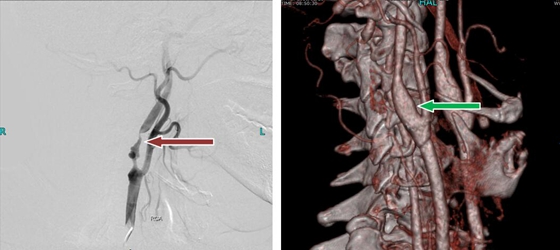

目前来说对高度怀疑存在颈动脉狭窄的患者进行颈动脉DSA是最为准确的,但由于这是有创的检查,且需要注射造影剂,很多人并不接受,目前仅作为特殊情况下检查。目前核磁共振及CT检查是较为常用的检查工具。